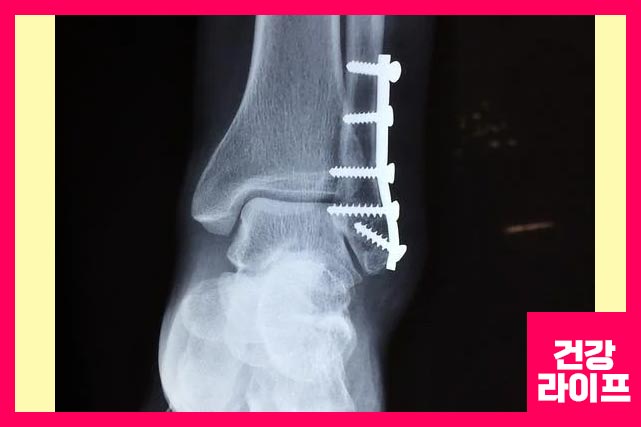

발목 골절

발목 골절은 경골이나 비골과 같은 발목에 있는 하나 이상의 뼈가 부러지는 것입니다. 발목 골절의 증상은 다음과 같습니다.